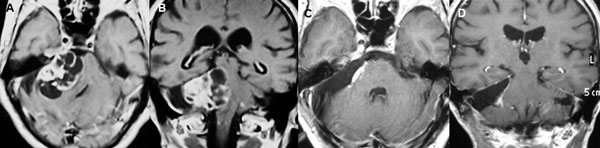

Figura 8: Paciente masculino de 62 años, operado de SV T4b multiquístico. A-B: RM preoperatoria. C-D: RM cerebral postoperatoria.